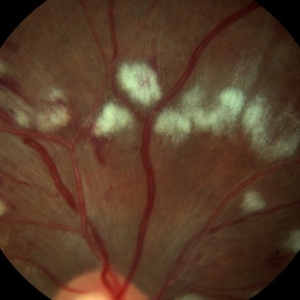

Arteriovenous Nipping, Cotton Wool Spots

Mar 1 2014 by Homayoun Tabandeh, MD, FASRS

Arteriovenous nipping, cotton wool spots in a patient with hypertensive retinopathy and diabetes

Condition/keywords: cotton wool spots